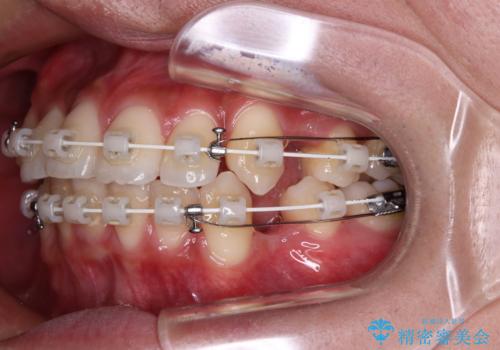

- 矯正装置

- 審美装置

- 八重歯と口元の閉じにくさを気にして来院された患者様です。

非抜歯矯正で歯列を整えると、治療後に口元が今よりも突出する可能性が高かったため、上下左右の第一小臼歯4本を抜歯し、ワイヤー装置にて矯正治療を行うこととしました。

患者様の望んでいた通りの歯列や口元に仕上げることができました。